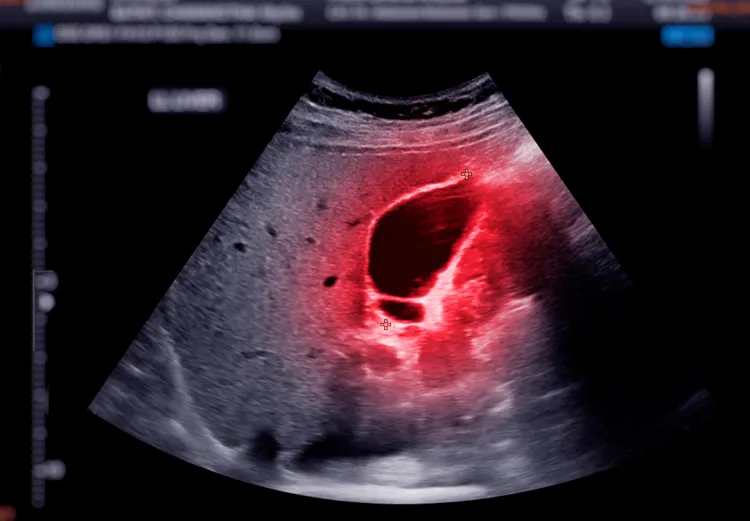

Incidência do cancro do pâncreas cresce mas investigação já permite curas iniciais

O oncologista da Fundação Champalimaud Carlos Carvalho alertou hoje que a incidência do cancro do pâncreas cresce nos países industrializados, com um aumento entre adultos, referindo que os avanços na investigação já permitem curas em casos iniciais.

Em declarações à Lusa, o diretor da Unidade de Cancro Digestivo na Fundação Champalimaud explicou que o cancro do pâncreas tem aumentado cerca de 1% ao ano na população geral, mas entre adultos dos 40 aos 55 anos, o crescimento anual varia entre 4% e 7%.

De acordo com Carlos Carvalho, apesar da elevada mortalidade, os avanços na investigação e tratamento do cancro do pâncreas já permitem curas em casos iniciais, ressalvando que a Fundação Champalimaud tem reforçado esforços para combater um dos tumores mais resistentes e agressivos.